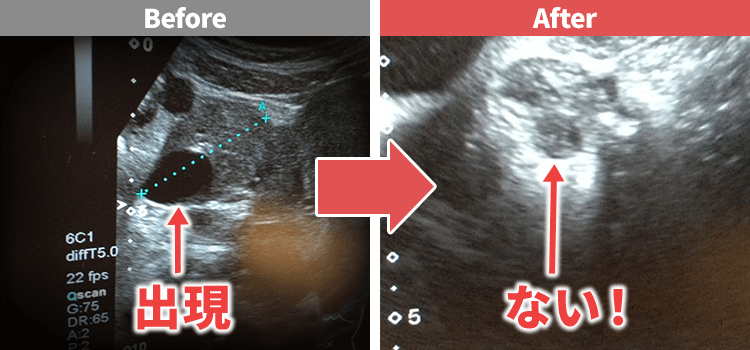

CASE3

肺にできた悪性の病気で

職場復帰は絶望的。

命すら危ぶまれる

危機的状況から…

たった数回の施術で改善!

夢だった職場への復帰が

叶いました!